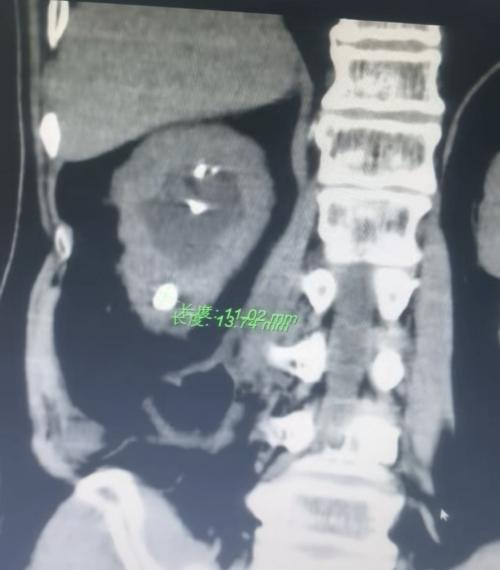

我科近期收治一名中年男性患者,因右肾下盏结石反复引发炎症导致腰痛,就诊后表达了对微创治疗的需求。

术前↑